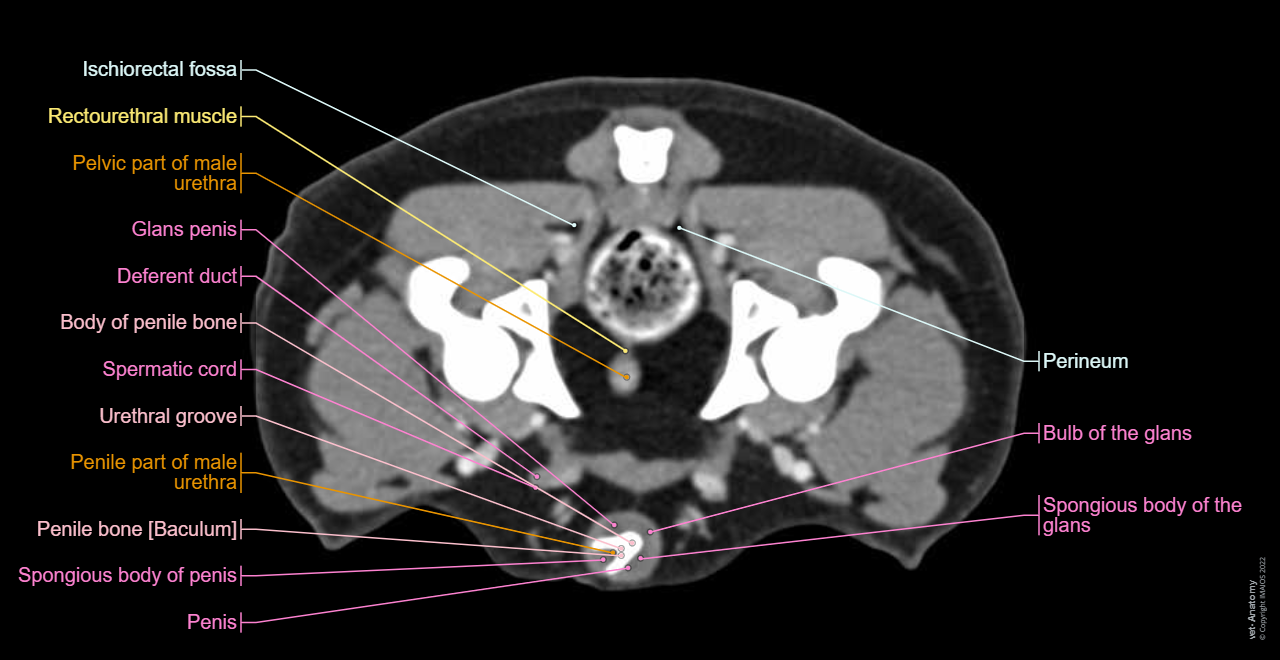

Cross-sectional labeled anatomy of the abdomen and male pelvis of the dog on CT imaging (liver, hepatic segmentation, pancreas, biliary tract, digestive tract, small and large intestine, kidney, bladder, genital organs, peritoneum)

Dog - Pelvis - Perineum - Anatomy

Dog - Coxal bone - Penile bone [Baculum]